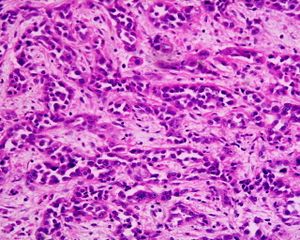

| A suspicious stomach ulcer that was diagnosed as cancer on biopsy and resected. Surgical specimen. | |

ـ التنطير الهضمي والخزعة: مع التطور الكبير في مجال صناعة المناظير الضوئية الليفية المرنة flexible fiberoptic endoscopes، صار من السهل إجراء فحص كامل ودقيق لمخاطية المعدة، ومشاهدة التغيرات المرضية، ومنها سرطان المعدة، مباشرة، وكذلك أخذ خزعات متعددة منها من أجل التشخيص النسيجي. ويجب أخذ 4 إلى 6 خزعات من أي آفة مشبوهة في المعدة لرفع دقة التشخيص.